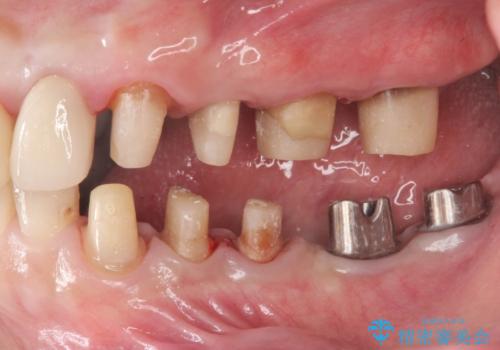

虫歯だらけの歯を治療したい

- 「虫歯が多発し、治療が終わらない。歯も無くなったし今後悪くならないような治療をしたい。」と精密治療を希望され来院されました。

虫歯の徹底的な除去やセラミック補綴、精密根管治療、歯周外科を行うことで、治療後に歯磨きがしやすく、かみやすい機能的な仕上がりへと導きます。